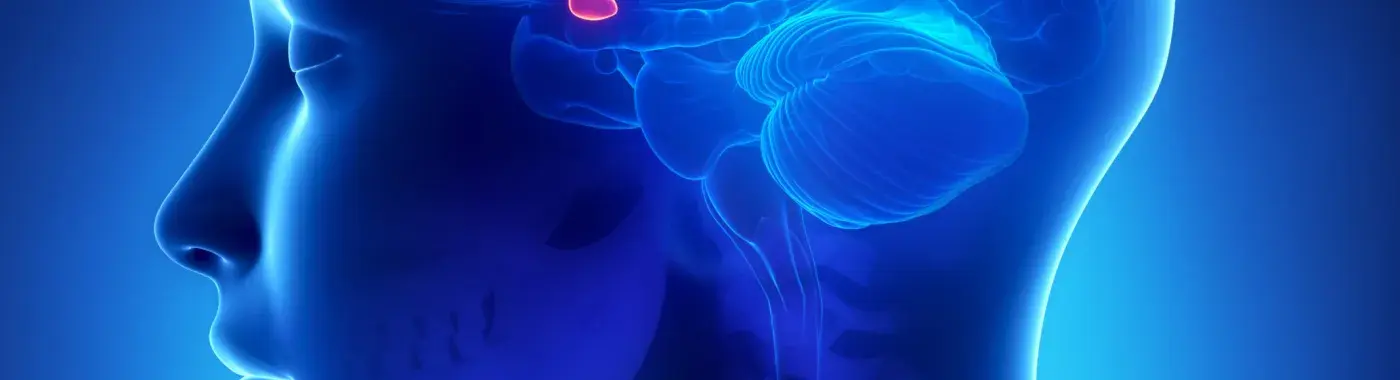

In Sheehan’s syndrome, women lose drastic amounts of blood while giving birth to a child or have low blood pressure reducing the oxygen supply to the woman. The deprivation of oxygen damages the pituitary gland. It is called Sheehan’s syndrome.

The pituitary gland produces pituitary hormones helping in the proper functioning of metabolism, reproduction, growth, blood pressure, and sexual maturation. But Sheehan’s syndrome doesn’t allow adequate production of pituitary hormones, which gets defined as hypopituitarism. It impacts the health of the mother, and lifelong artificial replacement therapy may get needed.

All these hormones get stimulated by the pituitary gland. Hence, its damage impacts the production of all these hormones that, in turn, have various repercussions.